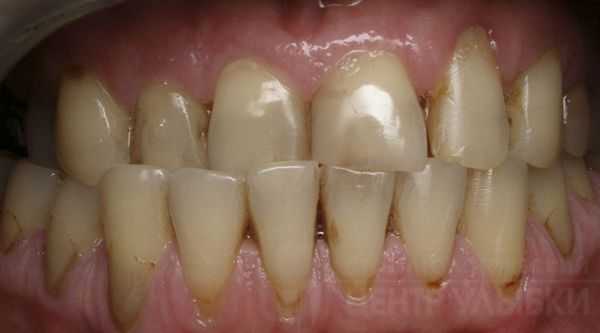

Пациент А. А., 18 лет. Диагноз: СЗЧЛА. Мезиальный прикус. Адентия верхних боковых резцов. Дистопия 45-го зуба.

Установлены элементы несъемной замковой ортодонтической техники на обе челюсти. План лечения на первом ортодонтическом этапе мог существенно различаться. Если в отношении перемещений на нижней челюсти разногласий быть не могло, то мероприятия на верхней допускали два варианта. Первый — раскрытие межзубных промежутков в области отсутствующих 12 и 22-го зубов с последующим протезированием. Второй — консолидация зубного ряда, предполагающая в дальнейшем эстетическую реставрацию верхних клыков, занявших положение боковых резцов.

Учитывая нежелание пациента сталкиваться с необходимостью протезирования по завершении лечения, а также стремление к изменению лицевых признаков аномалии за счет большей декомпенсации прикуса на первом этапе, был принят второй вариант.

Через 7 месяцев от начала лечения были установлены пассивные стальные дуги размером 0,17x0,25. Спустя несколько дней пациент был записан на госпитализацию.

Второй, хирургический, этап подразумевал проведение симультанного оперативного вмешательства на обеих челюстях: горизонтальная остеотомия верхней челюсти с ее выдвижением вперед и сагиттальная остеотомия ветвей нижней челюсти по Obwegeiser с перемещением ее тела кзади.

В послеоперационном периоде осуществлялась детализация положения зубов, создание окклюзи-онных контактов. Для улучшения смыкания зубных рядов выполнена сепарация аппроксимальных поверхностей 13 и 23-го зубов до соответствия их мезиодистальных размеров размерам отсутствующих боковых резцов. Особое внимание было уделено созданию резцового перекрытия для стабилизации результата.

В настоящее время лечение завершено (1 год ретенции). Удалены элементы ортодонтической техники. Установлены несъемные ретейнеры.